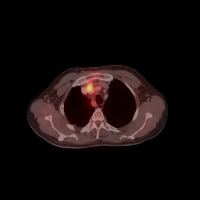

Diagnostic Aid in Medical Imaging: Radiologists could use this model to identify and characterize lymph node tumors in CT scans, assisting in early detection and diagnosis of potential cancerous growths.

Medical Research: Researchers might employ the model to study the characteristics and progressions of various types of lymph node tumors, towards producing more effective treatments and prevention strategies.

Training Medical Students: This model could serve as an invaluable tool for training medical students or residents in radiology, allowing them to familiarize themselves with the appearance and location of different lymph nodes, as well as to recognize varied tumor classifications.

Telemedicine: In remote or rural areas lacking immediate access to expert radiologists, this model can come handy as it assists primary care providers or mid-level practitioners in identifying lymph node tumors and making more effective referrals.

Second Opinion: Patients with possible lymph node tumors might use the model as a 'second opinion' to verify diagnoses, ensuring there are no oversights in their scans.